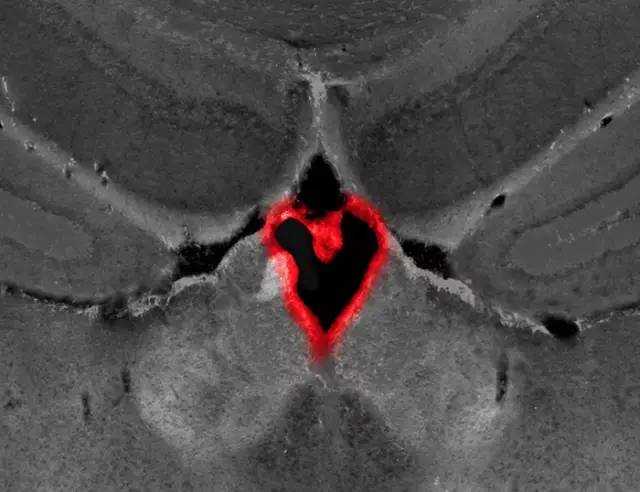

上图是大脑中部脑室充满的流体,其中细胞(脉络丛)形成了一个心脏形状。(来源:Burne 实验室客座研究科学家Dana Bradford)。